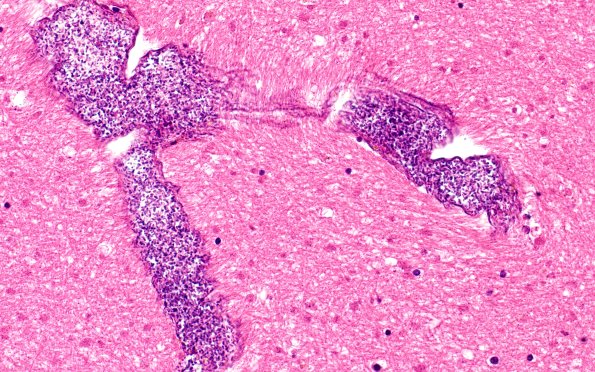

34B4 Swiss Cheese Brain (Case 12) 40X 1

Higher magnification of image #34B3. (H&E)